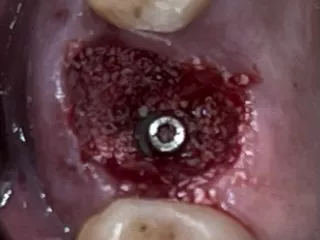

5. Occlusal view after atraumatic tooth extraction.

5

6. Immediate implant placement Ø 6.4mm Axiom® X3, 4 mm deep from the gum margin in the bone furcation for mucointegration.

6

7. Filling gaps with xenograft material

for socket preservation.

7

8. Occlusal view of the composite socket sealing with a 3mm provisional titanium retained SSA as fabricated by Gary Finelle.

8